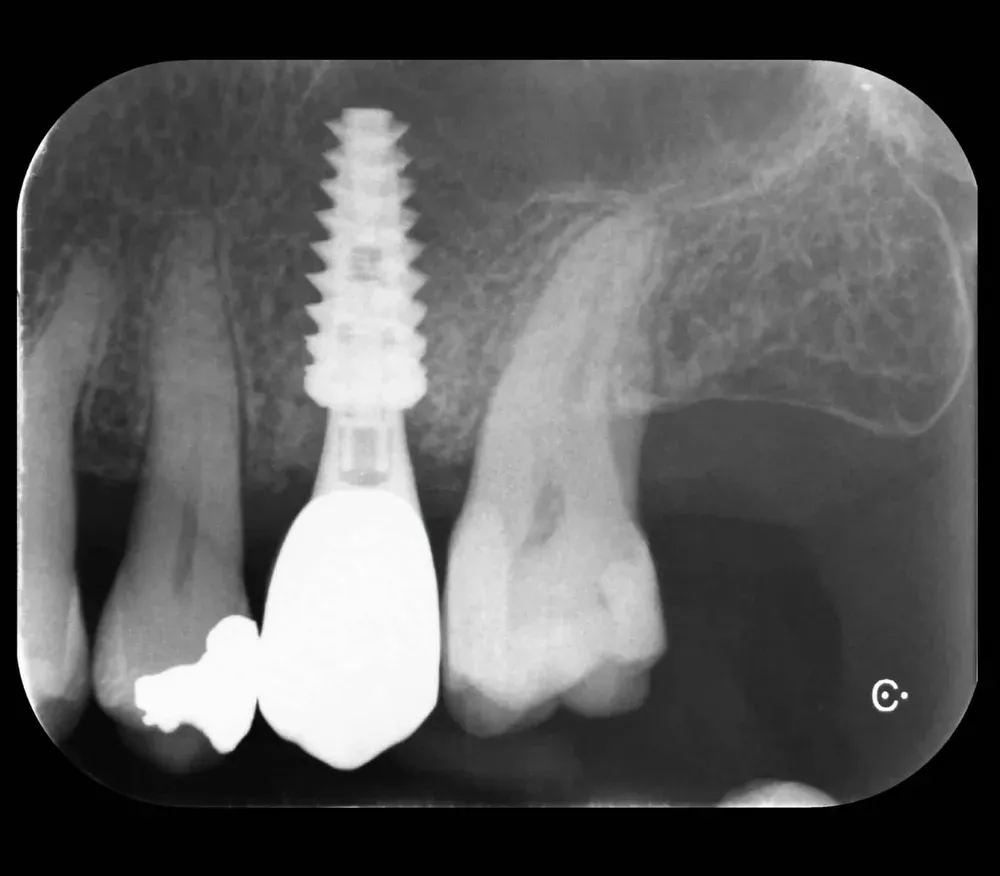

Per concludere il confronto tra le varie connessioni, l’immagine che segue è una radiografia con due impianti affiancati: un tissue-level ben posizionato fatto da un collega anni addietro e un impianto a connessione conica in posizione infracrestale con abutment della corretta lunghezza per il caso. Il secondo è un mio caso. È interessante notare come il cono dello spazio biologico sia identico. Se ben posizionati, tutti gli impianti funzionano egregiamente (l’impianto più vecchio inizia a soffrire un pochino, ma questa è un’altra storia).